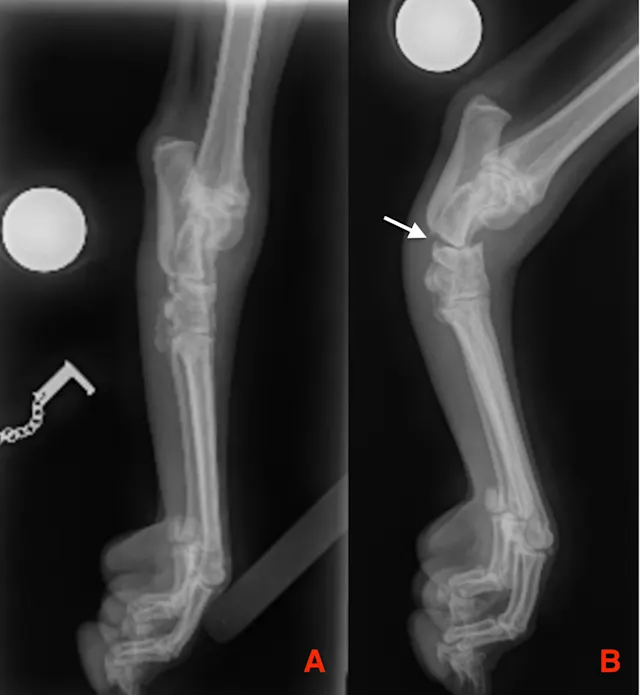

Carpal and tarsal injuries in cats and dogs are typically the result of trauma (eg, motor vehicle accidents, falling from a height) and are often accompanied by soft-tissue loss or shearing injury due to limited soft-tissue coverage of the distal limb (Figure 1).1,2 Immediate wound closure is thus not usually possible and often requires open wound management or skin reconstruction prior to addressing concurrent orthopedic injuries.

Degloving injuries seen following motor vehicle accidents, including on the medial aspect of the tarsus in a cat (A), the medial aspect of the tarsus in a dog (B), and the medial aspect of the carpus in a cat (C). The medial malleolus (A, B, arrows) is exposed.